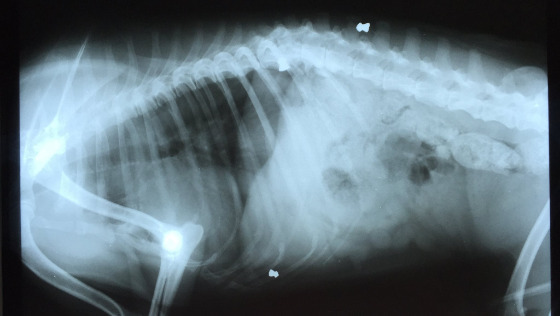

Zwierzę jest ofiarą bestialstwa i ludzkiego okrucieństwa. Ten staruszek ma w sobie trzy śruty! Jeden utkwił w kręgu !

To są stare postrzały, ale teraz psiak cierpi z powodu bólu kręgosłupa. Pies ma duże zmiany skórne, znaczne ubytki sierści, jest bardzo słaby. Został znaleziony na trawniku przed jedną z posesji w Płocku. Nikt z mieszkańców nie przyznał się, że jest właścicielem Dziadka. Zwierzę nie ma budy, śpi na ziemi i dokarmiane jest przez okolicznych mieszkańców.

Dzięki zgłoszeniu interwencji do naszej Fundacji, piesek dostał swoją szansę na nowe życie. Na szczęście jest już bezpieczny w domu tymczasowym. Psiak został zbadany przez lekarza weterynarii. Zaobserwowano u niego kaszel. Lekarz zalecił w najbliższym czasie badanie krwi, rtg stawów, badanie serca.